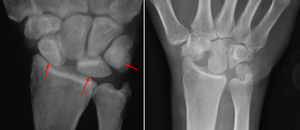

(Left) This x-ray of a healthy wrist shows normal joint space. (Right) In this wrist with osteoarthritis, the cartilage is worn and the healthy space between bones is narrowed.

(Right) Reproduced from JF Sarwark, ed: Essentials of Musculoskeletal Care, ed 4. Rosemont, IL, American Academy of Orthopaedic Surgeons, 2010.